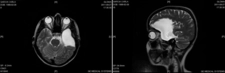

Bu belirtiler, lezyonun yerleşim yeri ve büyüklüğüne göre değişiklik gösterebilir. 4. Tanı YöntemleriYoğun içerikli kistik lezyonların tanısı, çeşitli görüntüleme yöntemleri ve biyopsi ile yapılabilir. Kullanılan başlıca tanı yöntemleri şunlardır:

Tanı Yöntemleri: Ultrasonografi ve manyetik rezonans görüntüleme (MRG) gibi tanı yöntemlerinin etkili olduğunu deneyimlemiş olmanız, bu süreçte ne kadar önemli bir yere sahip olduklarını gösteriyor. Bu yöntemler, lezyonların doğru bir şekilde değerlendirilmesi için kritik öneme sahiptir.